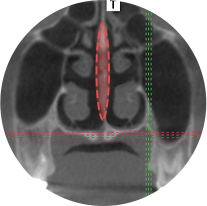

また、3D-CTと精密な診断で鼻の中の空間、鼻中隔の形などを観察し

機能的にも楽になる手術を目指しています。